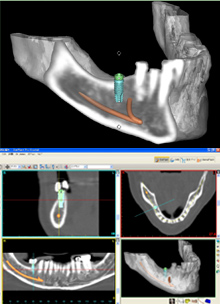

SimPlant(シンプラント)

SimPlantとは、3Dコンピューターシミュレーションシステムのことで、インプラント手術のシュミレーションを行うためのソフトです。

従来のレントゲンのみで診断する平面画像では、内部の骨の状態を正確に把握することが困難でした。

シュミレーションでは、歯科用CTで撮影した画像を処理し、レントゲン画像では分からなかった骨の形や量などを把握でき、正確な診断が可能となります。

また、3D画像は患者様が見ても比較的わかりやすいので、治療の説明もより理解していただけ、充分に納得した上で、手術を受けていただくことができます。